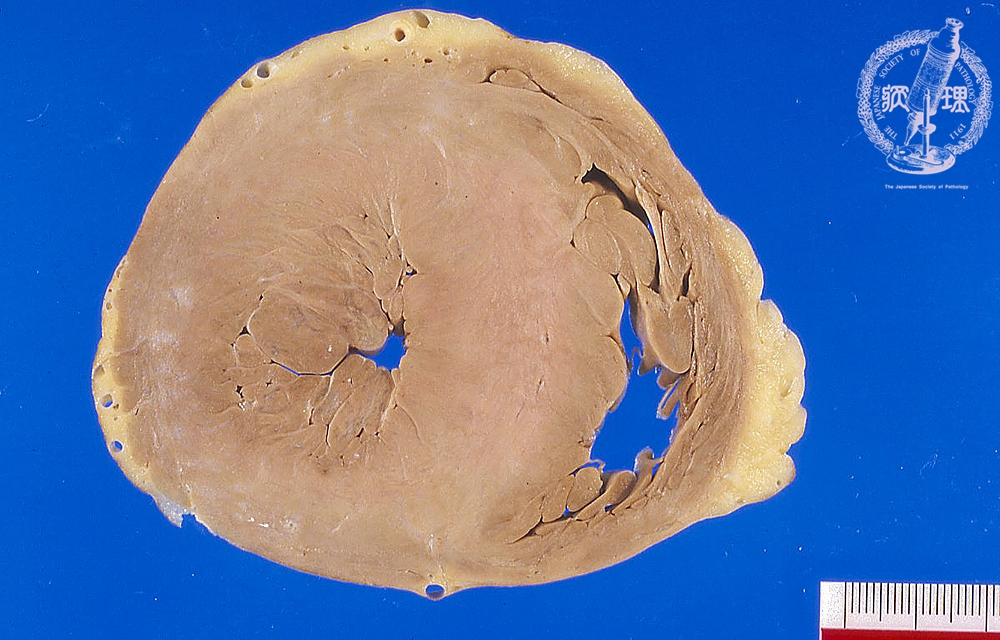

Macroscopic view (Hypertrophic cardiomyopathy): CT cross-section at the ventricular level shows striking left ventricular cavity narrowing and prominent thickening of the ventricular septum (normal thickness is around 15 mm).Please click here to compare with dilated cardiomyopathy.